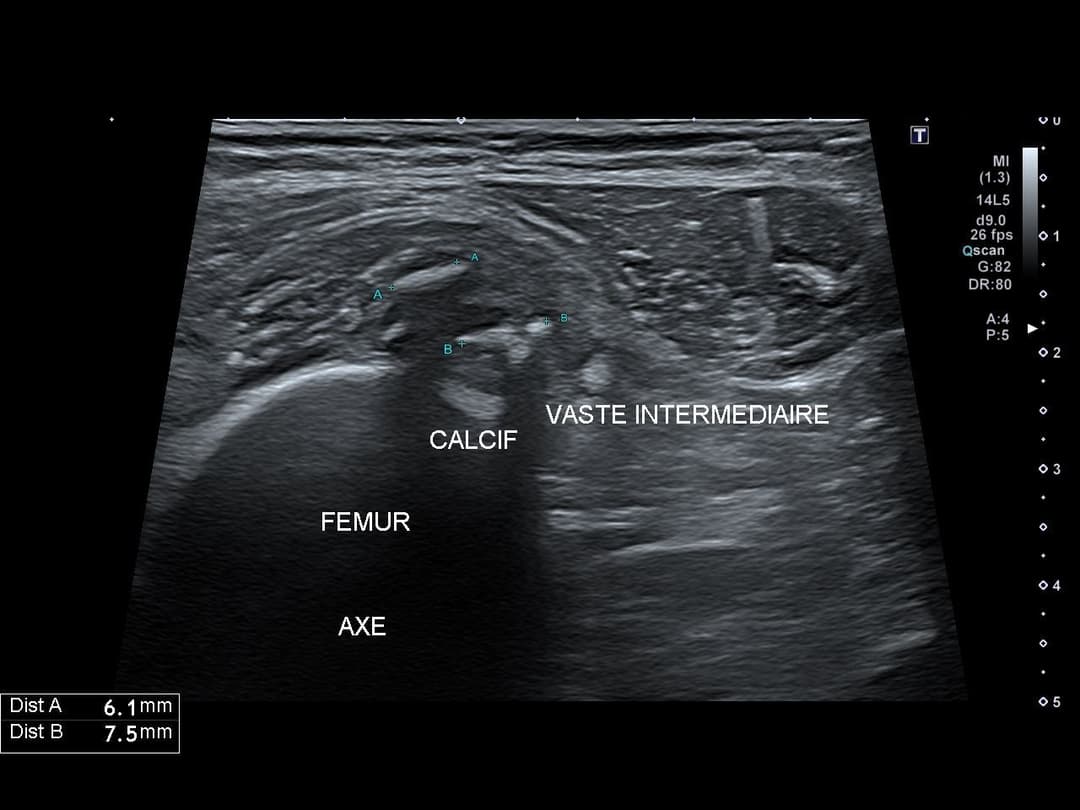

Myosite ossifiante du quadriceps

Patiente de 60 ans présentant une gêne persistante de la cuisse droite malgré un traitement par kinésithérapie bien conduit, suite à une chute à vélo il y a 2 mois

Échographie

Myosite ossifiante du vaste intermédiaire de la cuisse droite à 2 mois